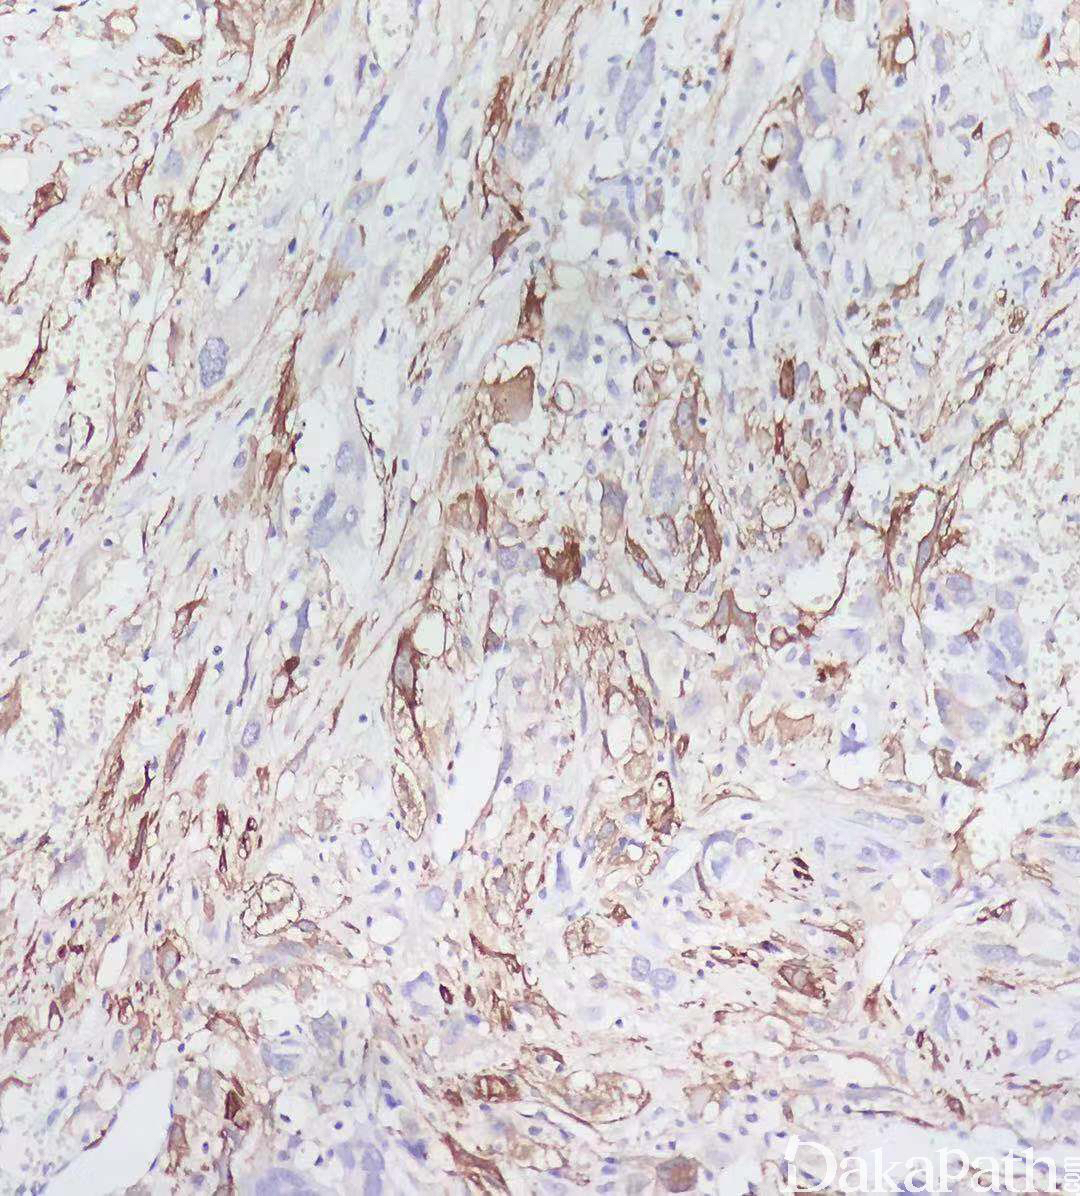

免疫组织化学染色:

α-SMA、MSA(HHF3 5)、h-caldesmon 和 calponin、P16 弥漫强阳性,多数病例 desmin 阳性,半数左右可表达 CD34(通常比较局灶),少数病例可表达 S100 和 EMA,CDK4 和 MDM2. HMB45. CD117 等阴性。